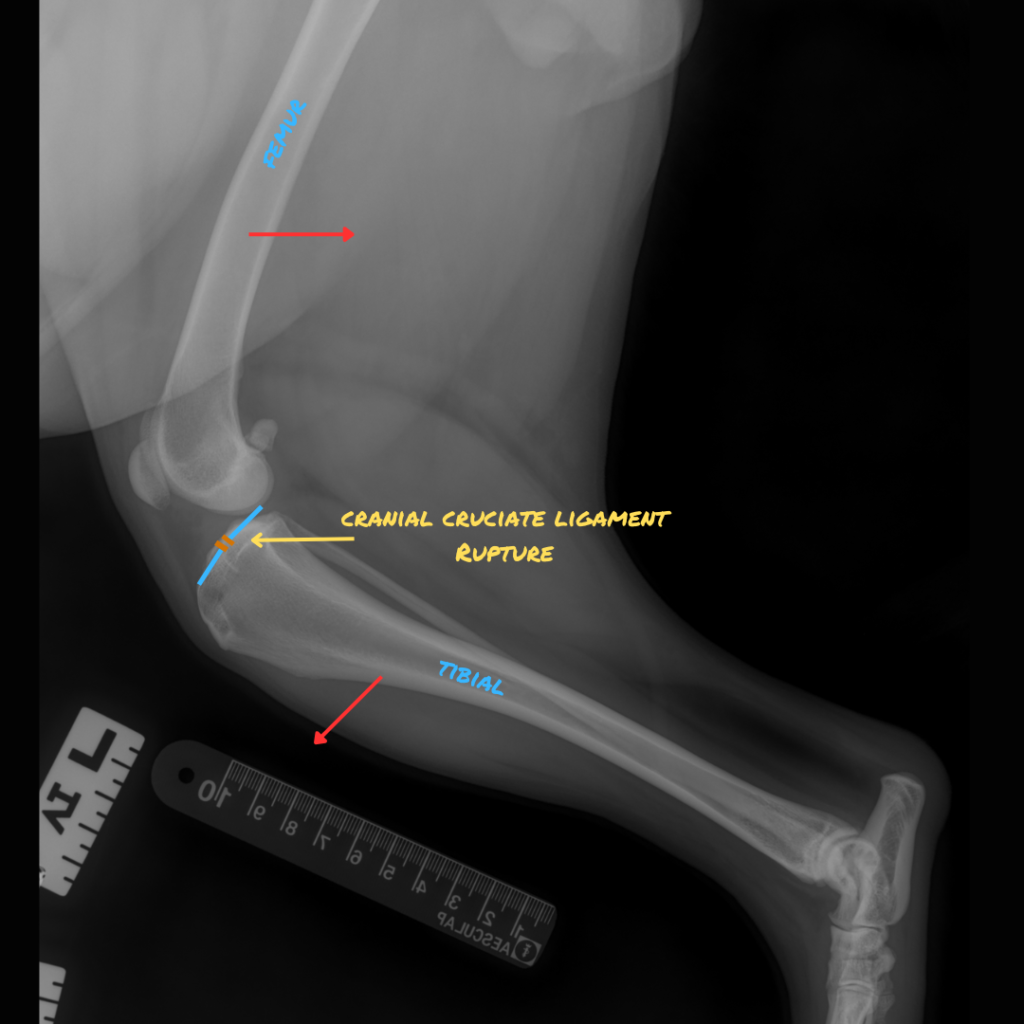

Cranial Cruciate Ligament Rupture